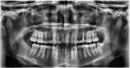

Судя по снимку, зуб запломбирован качественно.

Возможно, зуб отреагировал на воспаление в области лунки 3.8. Также по снимку видно, что корень данного зуба очень близко находится к верхнечелюстной пазухе. Во время эндодонтического лечения могла произойти перфорация дна пазухи, но судя по данному снимку, верхнечелюстная пазуха не пострадала.